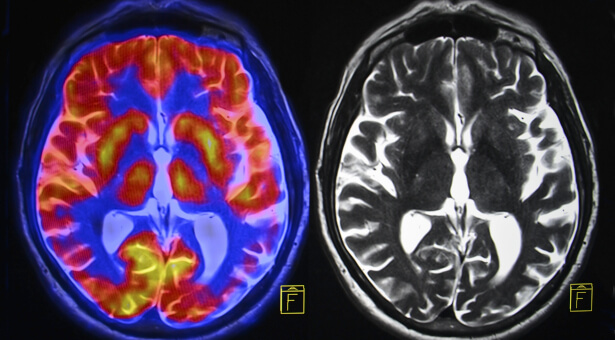

Mais c’est quoi au juste l’intuition ? Vue parfois comme un pouvoir magique ou comme une faculté réservée aux femmes, l’intuition n’a pourtant rien de paranormal et concerne tout le monde. Elle est la manifestation de notre cerveau qui fonctionne autrement que lorsqu’il emprunte la voie de la raison.

Les neurosciences se sont emparées du phénomène. L’intuition, mécanisme inconscient, a notamment été étudiée par le professeur de psychologie américain John Kounios qui explique comment certains de ces moments d’illumination ont même changé la face du monde en rendant possible découvertes et autres inventions. Pensons au fameux « Eurêka » d’Archimède !